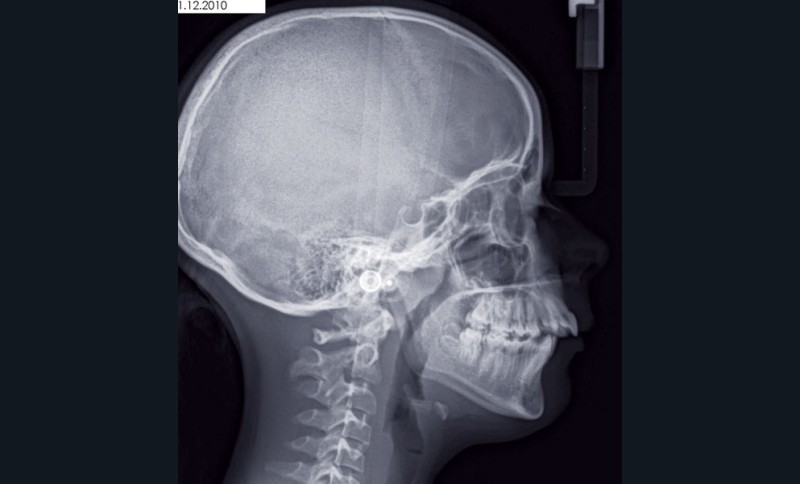

Camille âgée de 12 ans et 7 mois se présente à la consultation adressée par son chirurgien-dentiste.

Son profil convexe s’inscrit dans un contexte de rétrognathie hyperdivergente associée à une proalvéolie et un encombrement maxillo-mandibulaire.